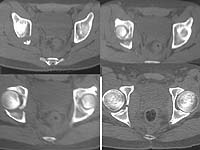

The CT showed a max displacement of 5 mm. Iliac and obturator views are obtained.

AP Pelvis

Iliac View

Obturator View

CT

After reviewing the Judet obliques and CT, I would tend toward nonoperative treatment. The maximum displacement is on the iliac oblique and the joint is certainly not perfectly congruent. However the femoral head seems nicely aligned to the acetabulum on all cuts of the CT and plain films.

I looked at the AP pelvis, Judet views, and CT you provided. This patient appears to meet all roof-arc criteria, and all ct-arc criteria (by my eval ~9 mm below vertex). The only question is late instability. I would follow the protocol of Tornetta et al for stress view under flouro (JBJS-BR 1999 January journal). If the femoral head stays congruent with the superior acetabular articular surface then non-operative management. (I think it will).